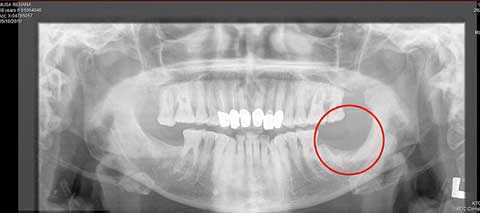

(VTC News) - Một cụ bà 72 tuổi đã đã được đền 2 tỷ đồng sau hơn 4 năm đau đớn vì bị nhổ 1 chiếc răng khôn.